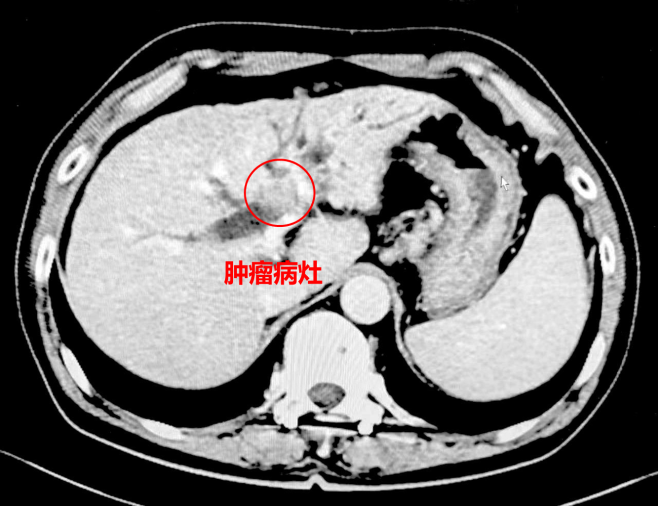

患者郭先生发现自己全身乏力,皮肤颜色越来越黄。在当地医院经过多天治疗未见缓解,来我院感染科就诊。在完成一系列检查后,感染科党双锁主任、李亚萍主治医师分析患者病情,认为患者存在肝门部胆管占位,请移植外科会诊后转科接受手术治疗。

由于患者有乙肝肝硬化,增加了术中大出血及术后肝功能不全的风险。在刘昌教授指导下,经过周密的手术规划和术前准备,蒋安主任医师、曲凯副教授带领移植外科团队于6月27日为患者实施腹腔镜下肝门部胆管恶性肿瘤根治术。手术先行肝门部肿瘤切除和肝门淋巴结清扫,再切除左半肝,最后再行腹腔镜下右肝管空肠吻合。麻醉团队陆阳、吕俊林医师,以及手术护理团队郭宁、兰天飞护师的娴熟配合,也保证了手术的安全顺利进行。